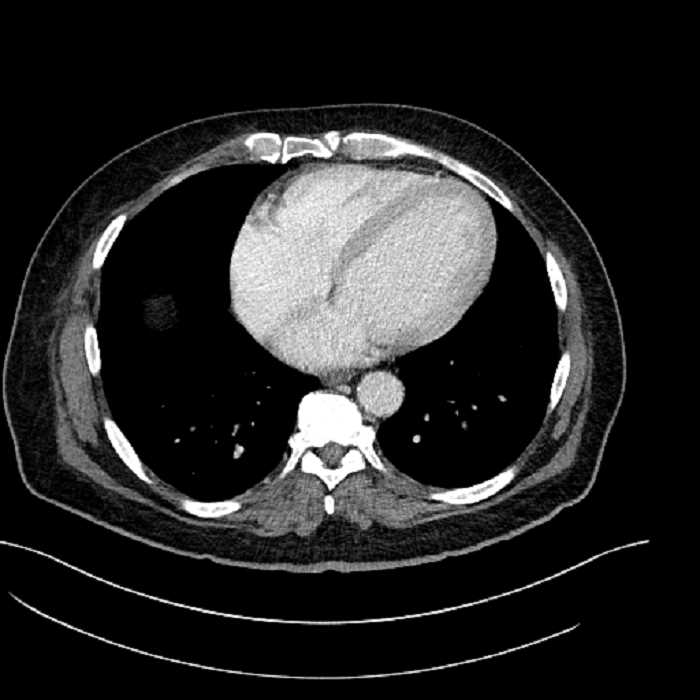

• Lower chest

• Mild cardiomegaly

• Mild dependent atelectasis

• The classic CT imaging appearance is a double target sign with internal low density surrounded by an internal enhancing rim (capsule) and a low density external rim (edema)

Hepatic abscess showing the double target sign with low density internally surrounded by a thin inner enhancing rim (red arrow) and ill-defined outer low density rim (yellow arrow). Blue arrow indicates an internal septation. Red arrows: additional smaller subcapsular abscesses. Red arrow: focal contained perforation associated with diverticulitis.